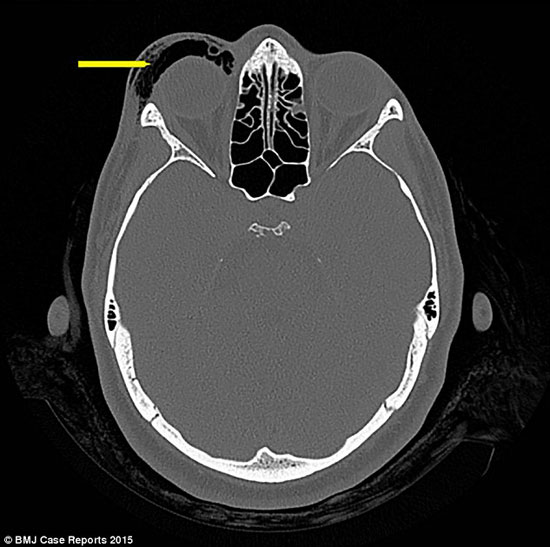

وأوضح التقرير الطبي انه بعد الفحص لهذه السيدة، تبين أن السبب وراء انتفاخ العينين إلى حجم كرة الجولف، نتيجة لتجمع الهواء فى الأنسجة الرخوة حول العينين، وتظهر هذه الحالة فى بعض الحالات التى تغلق أفواههم وأنوفهم لتطهير مجرى الهواء والفتحات المسدودة، وذلك فى أحد تمارين النفس المعروفة، بحسب صحيفة اليوم السابع.

اليوم السابع -10 -2015وألمح التقرير أن الرؤية لدى هذه المرأة لم تتأثر ولم يتضرر العصب البصرى، ويتم علاجها حاليا بالمضادات الحيوية ويمكن أن يزول التورم خلال أسبوعين من تلقى العلاج.